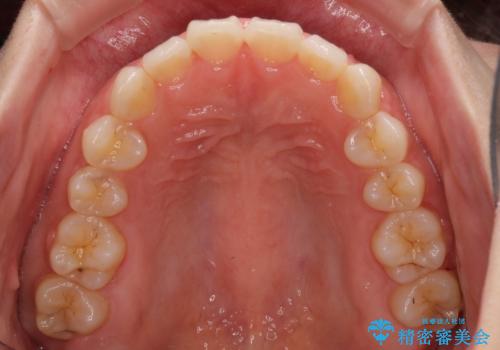

1日22時間の装着時間をしっかり守ってくださったので、1年程度で治療を終えることができました。

1セットのマウスピースで概ね治療を終えたのですが、前歯僅かな叢生が残ったため、2セット目のマウスピースで仕上げました。

気にしていた口元の印象が改善され、患者様には大変満足していただきました。